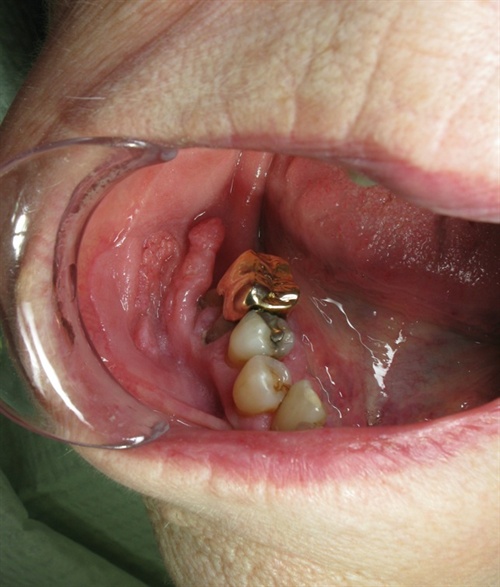

The images below are shocking, but show what can happen if you ignore your dentist's advice. This lady had a sore, slightly swollen gum at the back of her mouth. The first photo shows what the dentist saw.

Close up image of a person's lower right teeth and cheek, with a gold crown on the last molar and inflamed cheek tissue.the early appearance

In the image above you can see a flap of gum by the last two molars. It looks a bit odd, but not too serious, right?

Unfortunately, for personal reasons, this lady did not take her dentist's advice to see a specialist. She did nothing for over 2 years. Then she turned up at her dentist's office again, in a much worse condition.